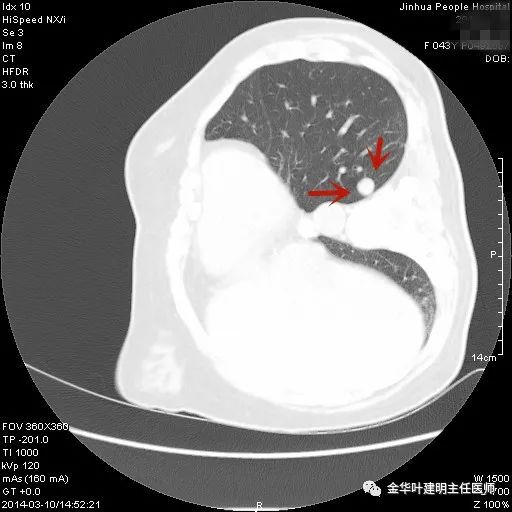

上图示胶原结节。我的理解是较慢性炎更向纤维瘢痕钙化发展,但仍未达钙化程度的一种状态(我不知道病理是不是这样)。该病灶表现为小而密度高的结节,边缘清晰,邻近胸膜却不牵拉,没有收缩力。